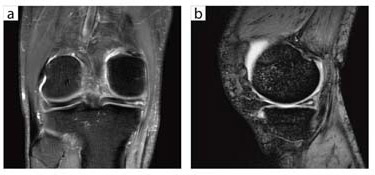

●関節への臨床応用

谷本:関節領域では,1.5Tよりも3Tの方がはるかに高画質です。特に,肩と膝の画質はすばらしいです。

奥田:腱の損傷を検出する際には脂肪抑制T2強調画像を撮像していますが,1.5Tでは高信号な部分は明瞭に描出されるものの,TEをやや短くしないと,背景の信号が弱く,解剖がよく見えないという状況でした。しかし3Tでは,TEを長くしたままでも背景の解剖のコントラストがある程度残るので,病変部位の同定が容易になりました。これは,S/Nの向上によるところが非常に大きいと思います。

谷本:3Tでは,前立腺やその他の領域もきわめて高画質が得られるようになりましたが,関節が最も1.5Tとの差が大きいかもしれません。

奥田:軟部腫瘍なども,LAVA-FLEXを使えば非常に均一に脂肪が抑制され,高画質が得られます。

谷本:最近では,SE法のT1強調画像は撮像しなくなりました。LAVA-FLEXのin-phaseで代用していますが,それでもまったく問題はありません。

![]() 図9 右膝内側半月板・水平断裂(QD Kneeコイル) a:FSE(2エコー)PD(脂肪抑制画像),FOV 16cm,スライス厚 3.5mm,3分32秒 b:T2*WI(MPGR),FOV 16cm,スライス厚 3.5mm,2分27秒 |